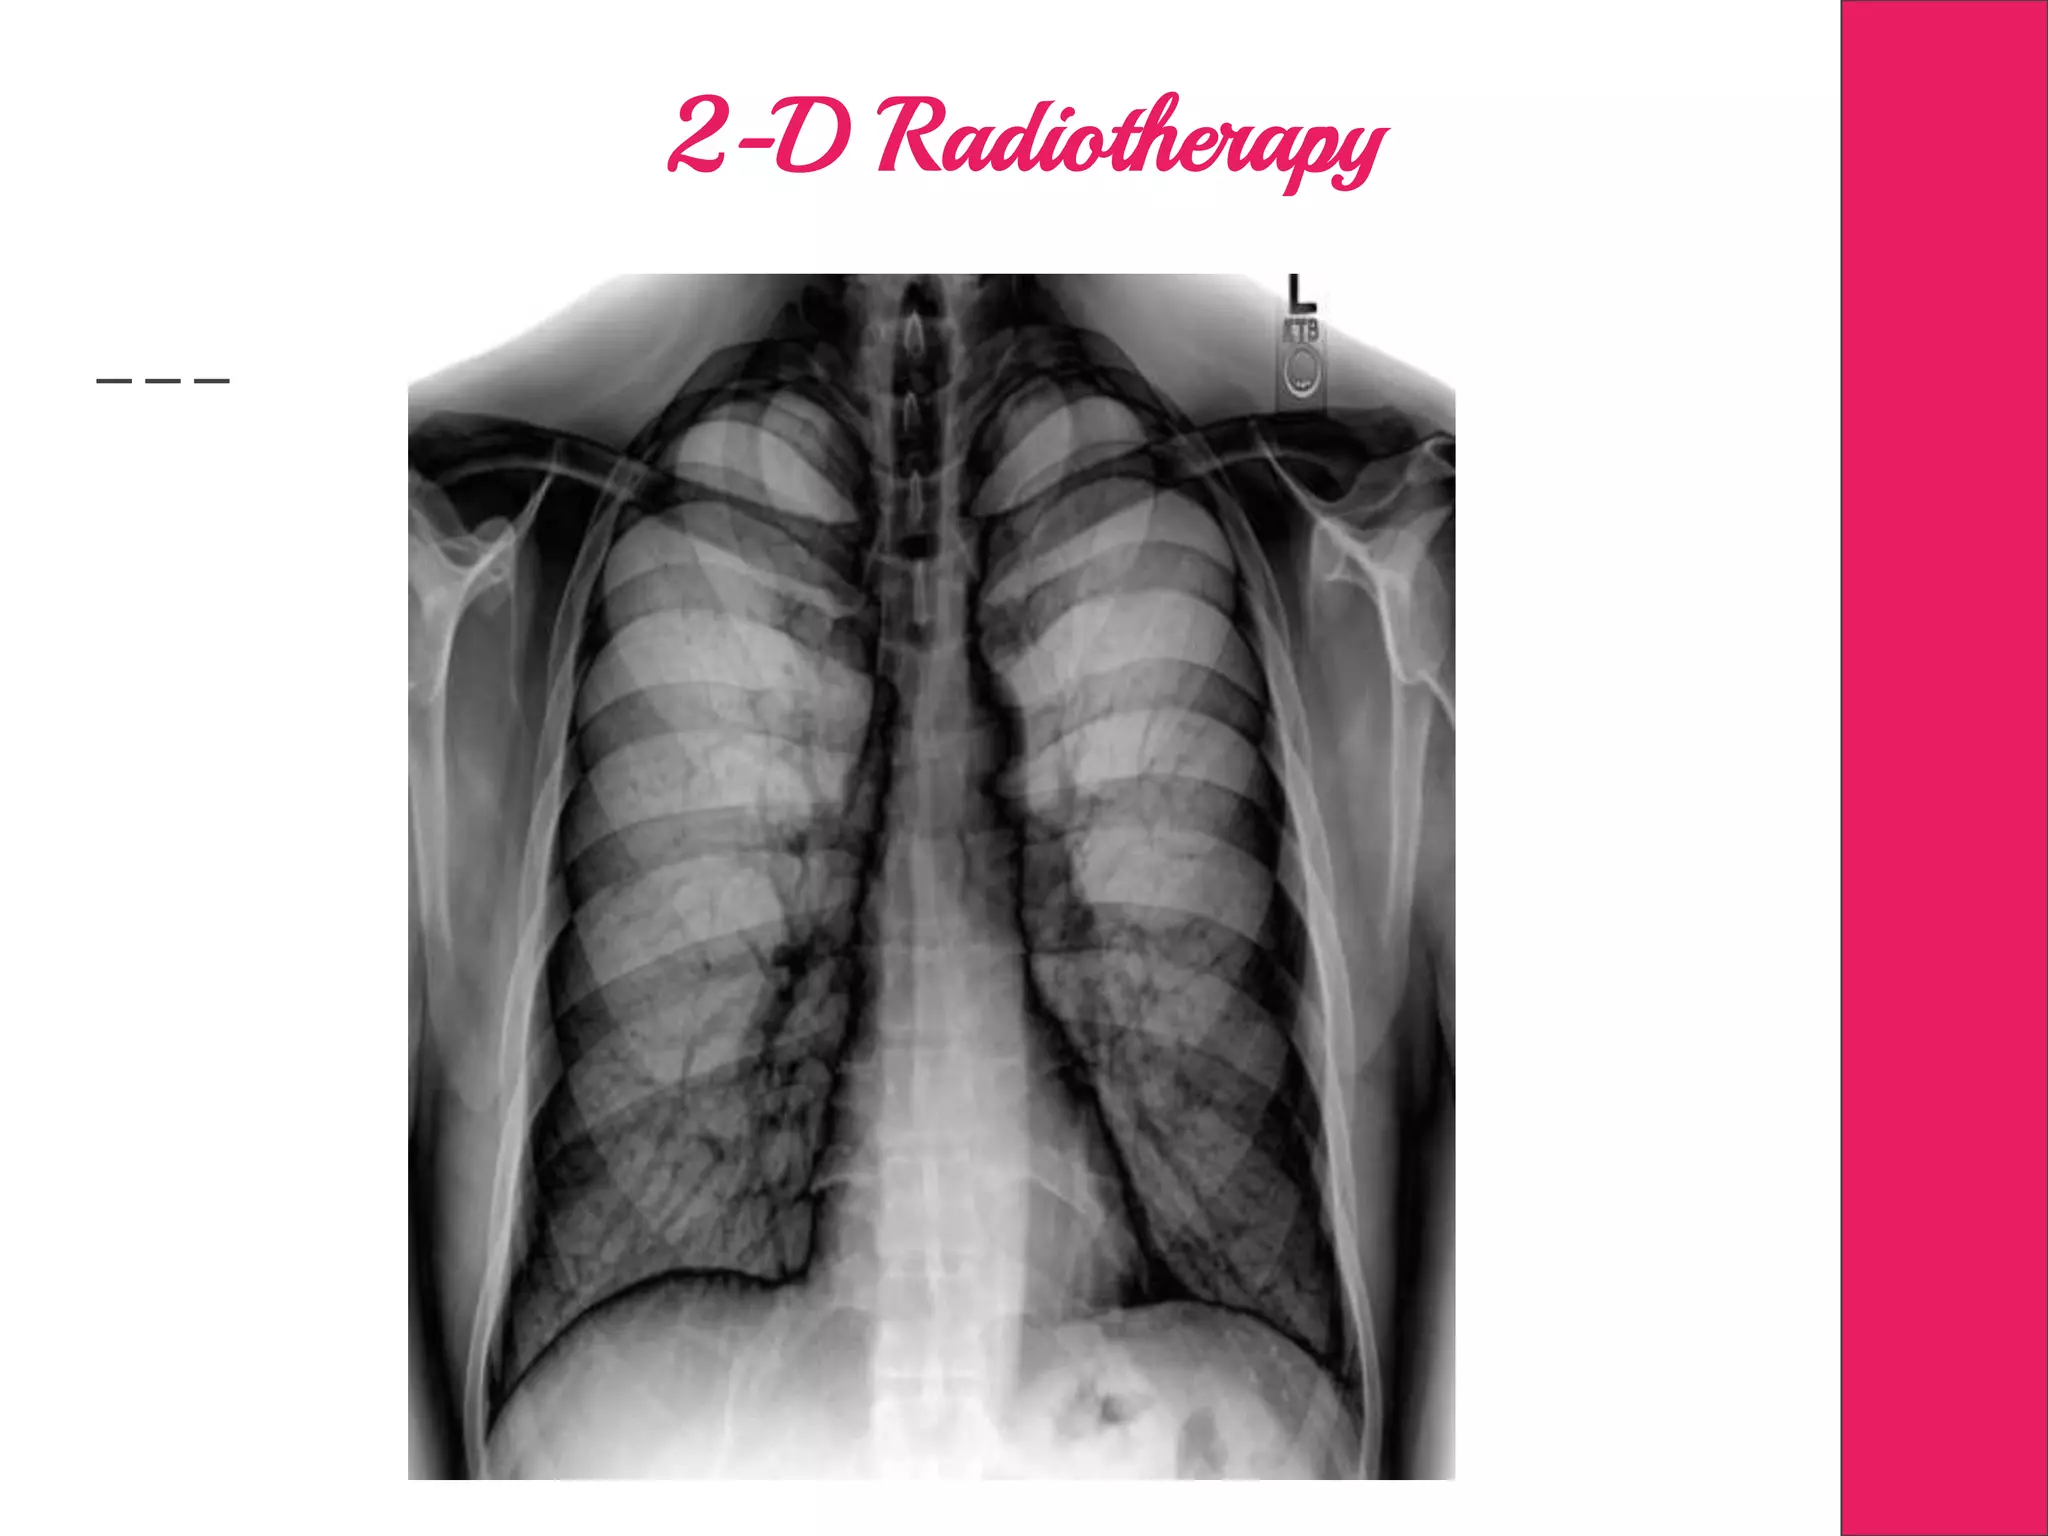

2-D Radiotherapy

Conformal Radiotherapy